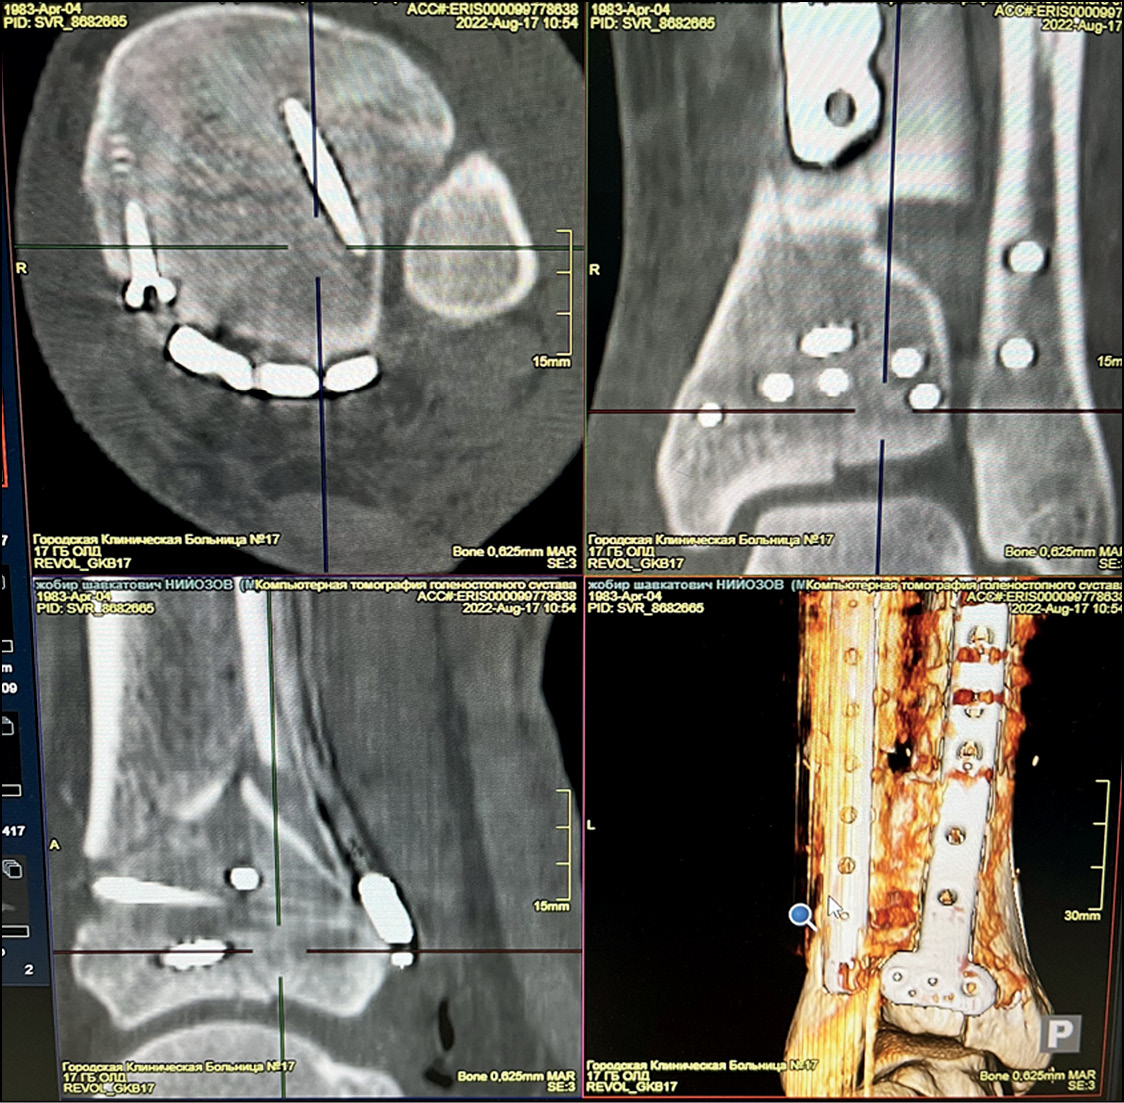

Через 7 дней осуществлён демонтаж аппарата, после чего пациент перевёрнут на живот и выполнена внутренняя фиксация метаэпифизов костей голени из заднелатерального доступа согласно разработанному предоперационному плану. Время операции составило 57 минут. Интраоперационная кровопотеря — 75 мл, количество снимков на электронно-оптическом преобразователе — 19. По критериям Burwell–Charnley качество репозиции хорошее (рис. 5).

Рис. 5. Данные контроля методом компьютерной томографии после операции.